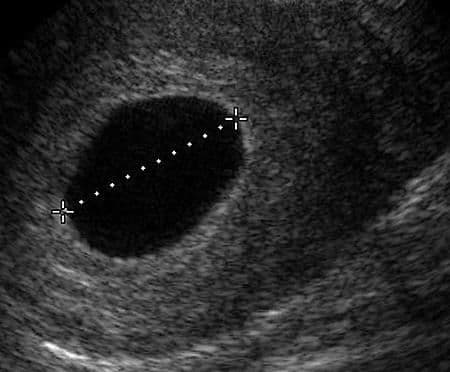

The gestational sac is the structure surrounding the fetus early in pregnancy and its shape early in pregnancy (usually before 8-10 weeks) is important. Ideally, the gestational sac should be round. But other shapes can also be normal, and there is no sure way of predicting what it means.

A normal gestational sac growth is about 1 mm per day after the 4th week of gestation. The mathematic formula for estimating the gestational age from measurements of the gestational sac is: Gestational age = 4 weeks plus (mean sac diameter in mm x days). For example, a gestational sac measuring 8 mm would be approximately 5 weeks and 1 day gestational age. (8mm equals 8 days; 4 weeks plus 8 days = 5 weeks and 1 day).